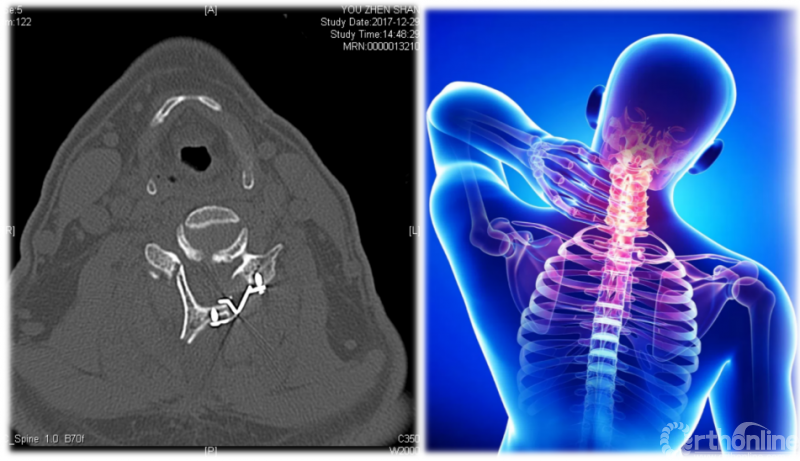

颈椎后路单开门椎管扩大成形术术后CT

首先,我们要提到治疗颈椎管狭窄、颈椎后纵韧带骨化的经典术式——颈椎后路单开门椎管扩大成形术(ELAP)。因其脊髓功能改善明显、疗效持久等优点,已被骨科医师广泛应用于临床,然而有些患者在手术后出现了长期的颈项部及肩背部疼痛、僵硬,并伴酸胀、沉重感和肌肉痉挛,严重时甚至影响患工作与生活。1999年Kawaguchi首次将这种病态定义为轴性症状(AS)。